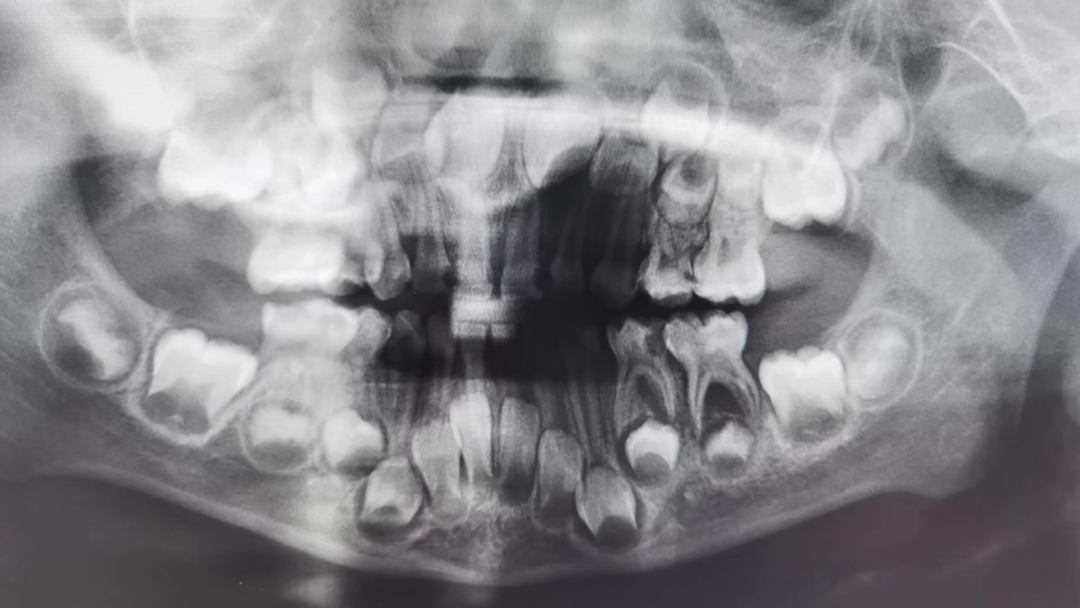

术前资料。通讯员 供图

近日,湖北航天医院口腔科儿童诊疗组接诊了一名“特殊”的患者——患儿5岁,全口20颗乳牙中有16颗不同程度的龋坏,其中三颗已经发展成根尖周脓肿,导致咀嚼疼痛,寝食不安。看过不同的医生,因患儿活泼好动,加上对治疗恐惧,不能很好地配合,治疗均半途而废,痛苦依旧。家长看在眼里,急在心上。

为缓解患儿的痛苦,消除家长的焦虑,以口腔科儿童牙医师李昀霏为主的治疗组联合麻醉科,在武汉大学人民医院儿童牙科王孜主任团队的技术支持下,于门诊儿童诊室开展了“全麻下儿童牙病的全序列治疗技术”。在70分钟的时间里,患儿平稳、安静“睡去”,医生操作有条不紊,根尖脓肿得到根治,龋坏得以修补,失衡的咬合得以恢复。